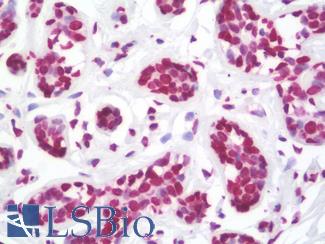

Estrogen Receptor / ESR1

Anti-ER Alpha / Estrogen Receptor antibody IHC staining of human breast. Immunohistochemistry of formalin-fixed, paraffin-embedded tissue after heat-induced antigen retrieval. Antibody LS-B10527 dilution 1:100.